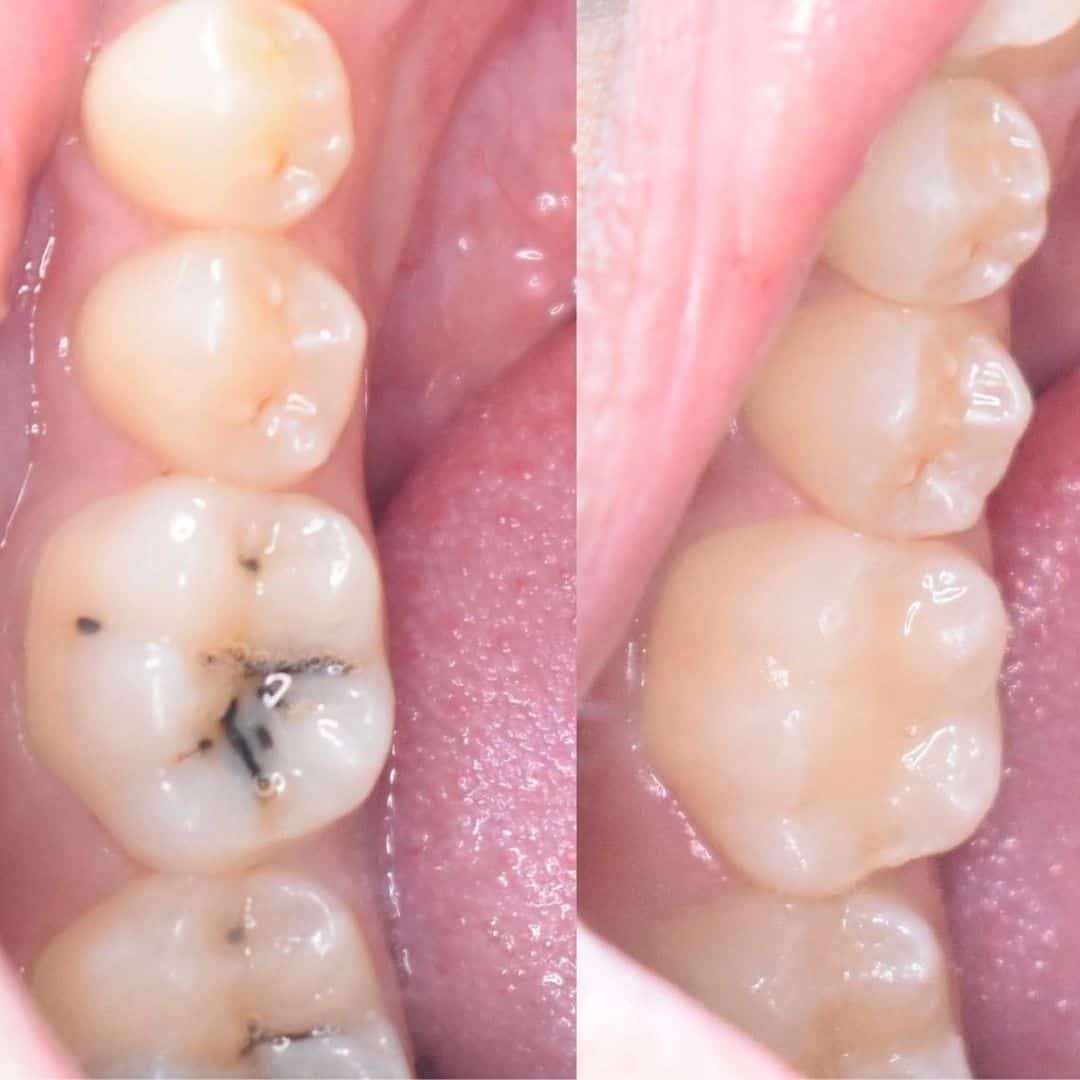

نتائج رائعة لمراجعينا